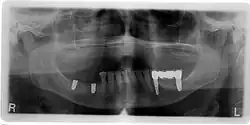

Planung

Die Planung einer Implantation geschieht je nach Komplexität der Situation mittels eines einfachen Zahnröntgens, oder durch Zuhilfenahme weiterer Hilfsmittel. Mit Hilfe einer Computertomographie (CT) oder einer Digitalen Volumentomographie (DVT) kann die Position des Implantats vor dem Eingriff festgelegt werden. Die Planung erfolgt dreidimensional am Computer und wird anhand einer individuell hergestellten Bohrschablone umgesetzt.[42] Nachteilig hierbei sind die Strahlenbelastung und die zusätzlichen Kosten für den Patienten.

Navigierte Implantologie

Die navigierte Implantologie ist ein prothetisch-chirurgisches Hilfsverfahren, um das richtige Setzen von Zahnimplantaten in den Kieferknochen zu erleichtern. Die Indikationen und Anwendungseinschränkungen für eine navigierte Implantation sind in den Guidelines der European Association of Osseointegration (EAO)[50] sowie für den deutschsprachigen Raum in der S2-K-Leitlinie der Deutschen Gesellschaft für Zahn-, Mund- und Kieferheilkunde (DGZMK) festgehalten.[51] Die meisten Indikationen beziehen sich auf eine Erweiterung der diagnostischen Möglichkeiten zur dreidimensionalen Darstellung der Kieferknochen und deren Nachbarstrukturen, um vor allem bei einem geringen Knochenangebot oder dessen unklarer Darstellung in den konventionellen Aufnahmetechniken eine verbesserte Einschätzung des OP-Gebietes zu ermöglichen.[42]

Im Vordergrund der Komplikationen stehen alle Faktoren, die eine Infektion im Implantationsbereich begünstigen. Zahnimplantate unterliegen der Gefahr einer Periimplantitis, einer Entzündung des Knochengewebes um das Zahnimplantat herum. Die Verbindung zwischen Implantat und Knochen ist nahezu ausschließlich durch bakterielle Einflüsse zerstörbar (Auflösung der Knochenmatrix durch Matrix-Metalloproteasen, MMPs). Die Ursache ist entweder auf Operationsfehler oder auf eine ungenügende Mundhygiene des Patienten zurückzuführen. Die Periimplantitis führt zu einem Knochenabbau, der letztendlich den Ausfall des Implantats bewirkt. Eine Zahnimplantation wird als Misserfolg gewertet, wenn das Implantat mobil ist oder einen periimplantären Gewebsschwund von mehr als 1 mm im ersten Jahr aufweist. Eine Periimplantitis kann durch prophylaktische Maßnahmen zusammen mit einer Antibiotikatherapie behandelt werden. Eine Periimplantitis ist auf einer Röntgenaufnahme zu erkennen.